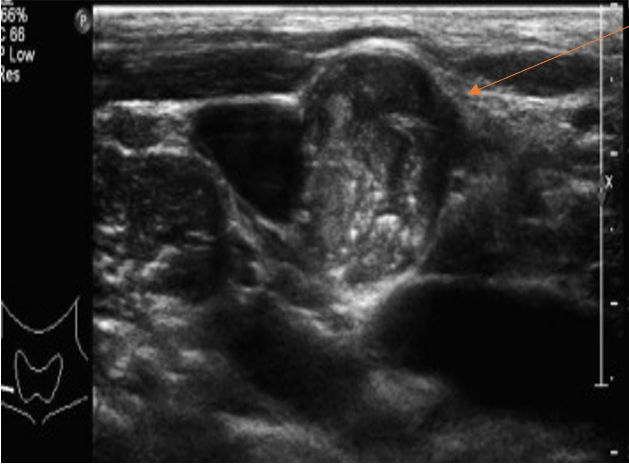

The most important step after the diagnosis of a thyroid nodule is the actual thyroid ultrasound. Preoperative ultrasonography US is the most sensitive method for detecting metastatic lymph nodes and is recommended as part of the standard preoperative workup. No single ultrasound feature can predict malignancy in thyroid nodules with acceptable diagnostic accuracy a new systematic review and meta-analysis suggest.

The American College of Radiology ACR recently published recommendations that use age nodule size and specific imaging features to determine which incidental thyroid nodules need further evaluation with neck ultrasound and which do not. The sound waves bounce off the organs inside your body and the microphone picks them up. During ultrasound the technician must thoroughly examine the thyroid and all the areas of lymph nodes in both sides of the neck that can be involved with thyroid cancer.

It is not clear whether these imaging tests can accurately predict thyroid cancer by themselves without the need for a neck ultrasound. Determining that a nodule is definitively benign or malignant is difficult and so when indicated a. This study suggests that ultrasound features of microcalcifications solid nodule and size larger than 2 cm can be used to identify patients at high risk for thyroid cancer.

It can detect clinically impalpable thyroid nodules and characterize them as cystic solid or complex. Optimal treatment of thyroid cancer is highly dependent on accurate staging of the extent of disease at presentation. In patients with a thyroid nodule suspicious for papillary thyroid cancer on ultrasound-guided FNA and with ultrasound features associated with malignancy the risk for thyroid cancer is very high 95 necessitating thyroidectomy.